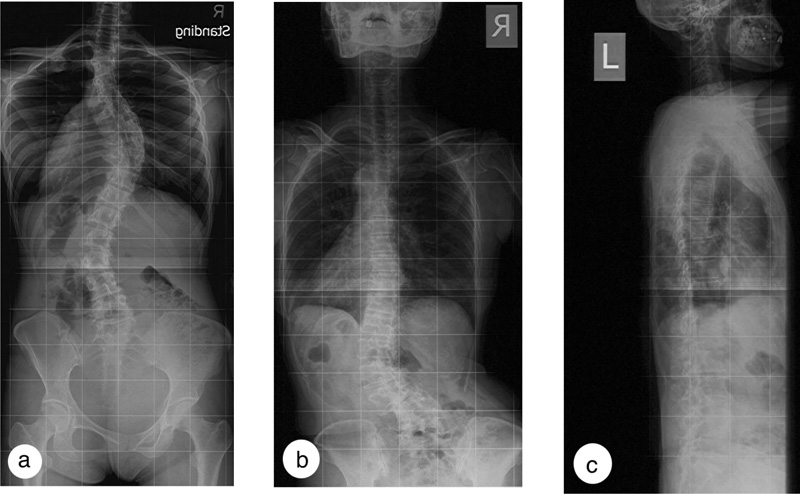

In many instances, patients do not have prior radiographs. Documentation of the rate of progression of the curve as a justification for bracing would thus be challenging, especially when adult IS patients have a long history of scoliosis, and progression over the years may not be linear [42, 43]. Therefore, it is proposed that adult scoliosis patients with sagittal imbalance, reduced lumbar lordosis, and radiological parameters associated with a higher risk of curve progression or low back pain are indicated for brace treatment (Fig. 2). It has to be noted that low back pain in a scoliotic patient does not equate that the pain must be related to scoliosis [44]. Before the brace prescription, a proper evaluation should ensure that the pain is secondary to the spinal deformity and not other causes.

Whether the brace should be accommodative or corrective depends on the deformities and spinal rigidity and not on the patients’ body habitus. At present, it is clinically challenging to grade lumbar rigidity. The presence of marked arthritic or osteochondral changes suggests an increased spinal rigidity. An accommodative brace should be prescribed when the curve is rigid [17, 18] or in the presence of rotatory olisthesis to help stabilize the spine (Fig. 3). When the elastic brace cannot provide the needed support because of a mismatch of the spinal contour, a custom accommodative rigid brace may be prescribed to provide spinal support and limit motion, particularly in patients with more severe curves. Coupled movements in the lumbar spines are higher in DLS patients, particularly with larger curves, in most loading directions than in the lumbar spine with no scoliosis [45].